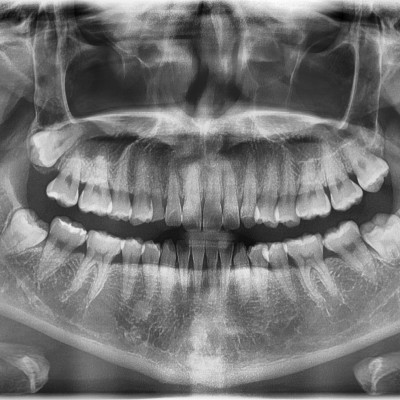

#18,28,38,48 사랑니 발치 #18,28,38,48 사랑니 발치 구강 외과 전문의가 당일 발치했습니다. ------------------..

작성자 이턱이 작성일 03-16 조회 12